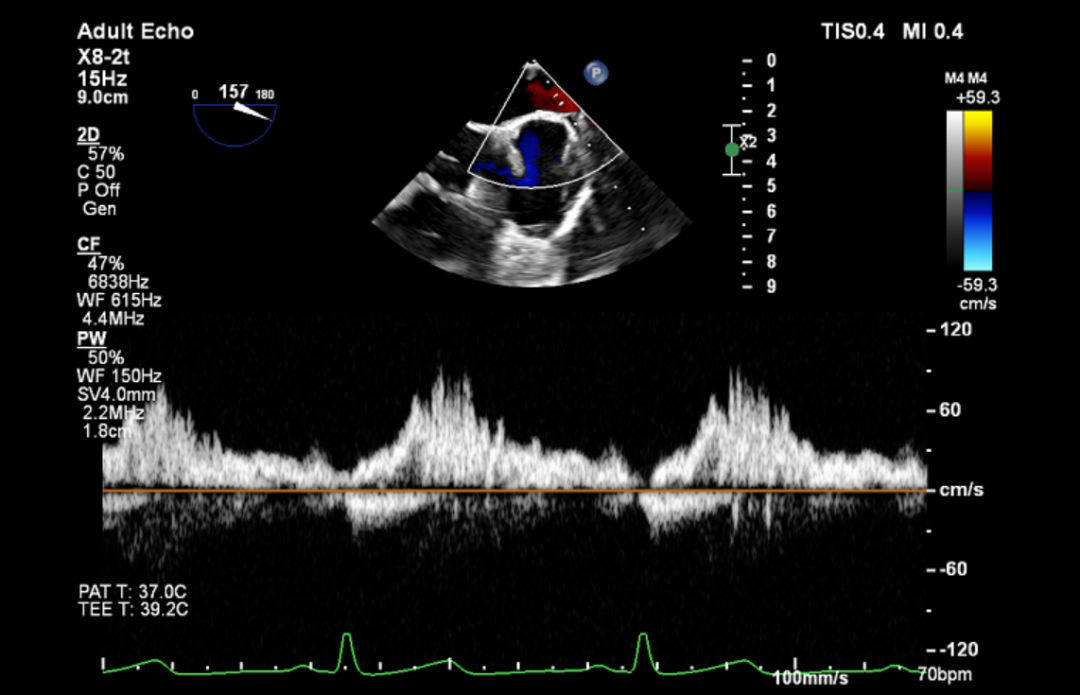

术前TEE评估

原发性二尖瓣反流(DMR),后叶P3区脱垂,反流程度4+,EROA 0.40cm2、RV 39ml;二尖瓣瓣口面积5.37cm²;二尖瓣前叶(A3)长度14.0mm,二尖瓣后叶长度(P3)长度12.2mm,脱垂宽度8.2mm,脱垂高度1.4mm;RA 2.9cm ,LA 3.6cm,左室射血分数LVEF56%,术前测量最大房间隔穿刺高度4.0cm

将MitraClip™XTR送入左房,由于左房太小,在达到骑跨过程中反复推进回撤CDS和稳定器,同时旋转SGC,达到骑跨的同时,保证Clip头端游离,且SGC在左房有深度。旋转M,同时顺时针往后旋转SGC借高度,使Clip垂直二尖瓣环平面,由于穿刺高度不够,Clip直接进入左室,这意味着操作要十分小心,左室组织复杂,稍有不慎将会造成组织损伤。使用A/P Konb中“A”旋钮借高度。确认垂直后,直接在左室打开Clip,3D外科视角,逆时针旋转使Clip夹臂处于11点-5点方向,回拉稳定器,使Clip处于3区脱垂区域,用“+/-”Knob中的“-”旋钮,使Clip更往后叶的同时增加操作高度,抓捕脱垂的瓣叶,关紧Clip后,反流从4+降低至0级,平均跨瓣压差2mmHg,左右肺静脉逆流均改善。前后叶活动度降低,后叶插入长度9mm,前叶插入12mm, 确认稳定性后释放Clip。释放后,即刻效果十分满意,手术圆满结束。